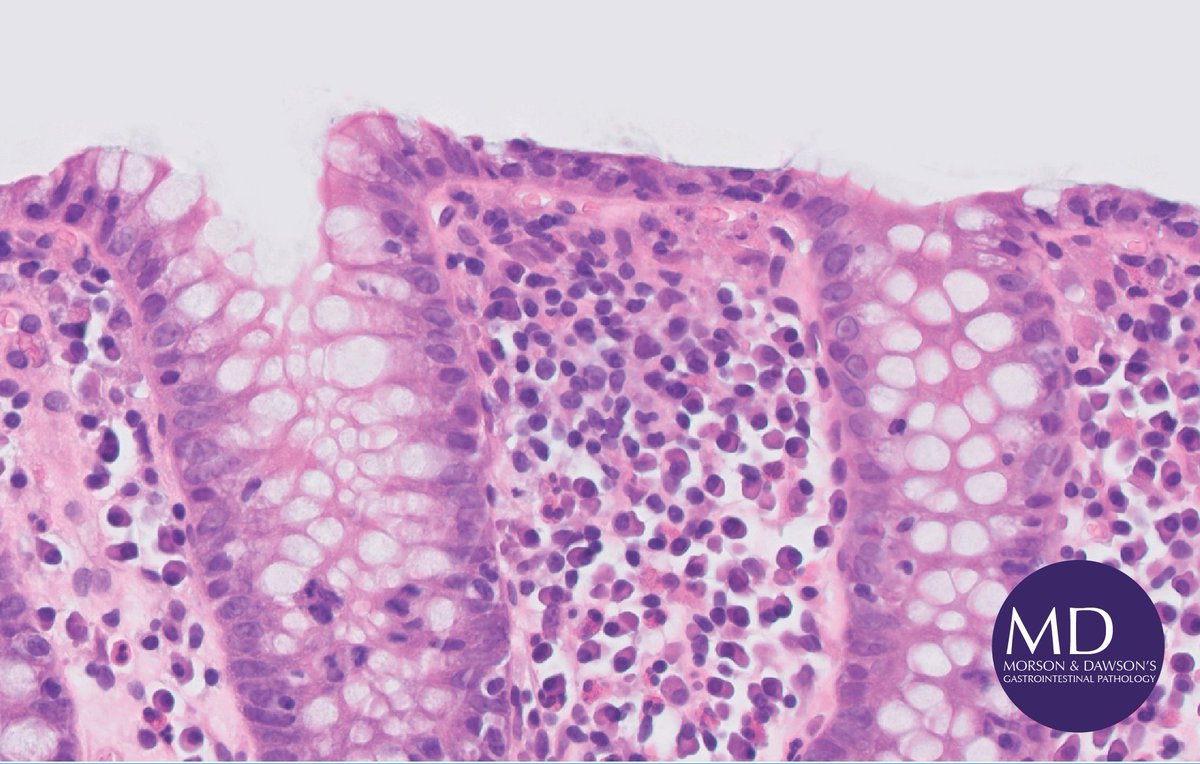

Elderly patient w/chronic diarrhoea on trial checkpoint inhibitors for cervical cancer. Normal colonoscopy (aside from mild telangiectasias, possibly radiotx related). Bxs show lymphocytic colitis consistent w/ immune checkpoint inhibitor colitis (see PMID: 29143108) #pathology